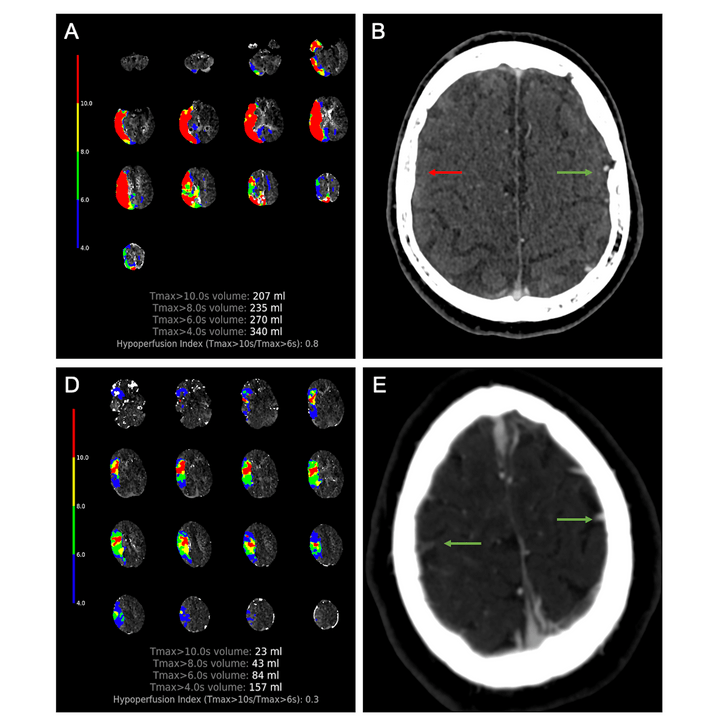

Perfusion imaging-based tissue-level collaterals predict ischemic lesion net water uptake in patients with acute ischemic stroke and large vessel occlusion

Faizy T, et al. (2021) JCBFM Feb 8;271678X21992200. doi: 10.1177/0271678X21992200.

CT perfusion core and ASPECT score prediction of outcomes in DEFUSE 3

Kim-Tenser M, et al. (2020) Int J Stroke Mar 31;1747493020915141. doi: 10.1177/1747493020915141.

Hypoperfusion Intensity Ratio Is Correlated With Patient Eligibility for Thrombectomy.

Guenego A, et al. (2019) Stroke. Apr;50(4):917-922. doi: 10.1161/STROKEAHA.118.024134